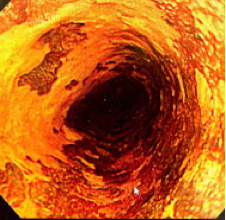

内科・内視鏡部との連携:当院内視鏡部は、「安全で確実、苦しくない内視鏡」をモットーとした内視鏡診療を行っており、現在日本で実施可能な最先端の高次内視鏡治療を積極的に実施しています。

早期大腸がんに対しては根治的な内視鏡的切除術(ESD/EMR)を積極的に行っております。昨年度の内視鏡的粘膜下層剥離術(ESD)は年間66件、内視鏡的粘膜切除術(EMR)は年間365件でした。内視鏡学会認定指導施設として常に高いレベルの診療が行われており、外科と緊密な連携のもと、診療にあたっています。